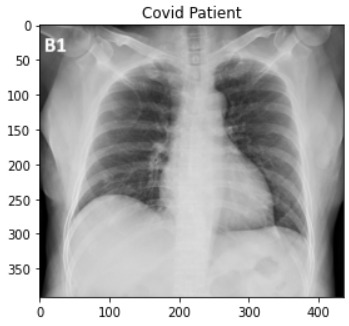

Our project is a simple image classification convolutional neural network (CNN) that deals with 3 classes of X-ray images (Covid-19 patients, Viral Pneumonia patients , and Normal patients)

Created an effective classification model for X-ray images of potential Covid-19 patients.